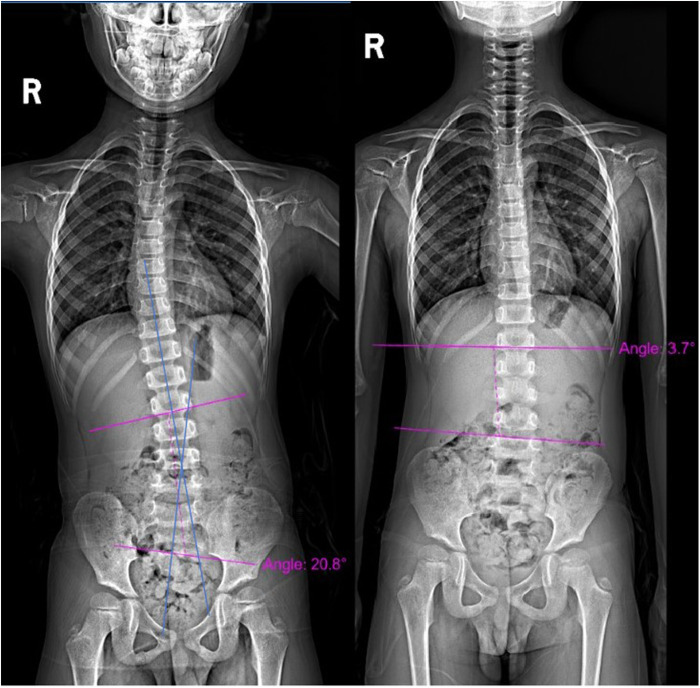

Methods: This retrospective cohort study included five prepubescent patients (age 10-14 years, Tanner Stage 1-2) with moderate AIS (Cobb angle 20°-40°). The intervention combined Schroth exercises with core exercises, performed 3-4 times daily over six months. Cobb angles were measured from standing full-spine radiographs at baseline and six months, while quality of life was assessed using the Scoliosis Research Society-22 (SRS-22) questionnaire.

Results: The mean Cobb angle significantly reduced from 24.12° ± 4.80° at baseline to 12.68° ± 8.11° post-intervention (p = 0.012). Quality of life improved across all SRS-22 domains, with statistically significant gains in pain (p < 0.001), function (p = 0.011), mental health (p < 0.001), and self-image (p < 0.001). These findings suggest that the combined intervention effectively addresses spinal alignment and muscle strength, leading to improved clinical outcomes.